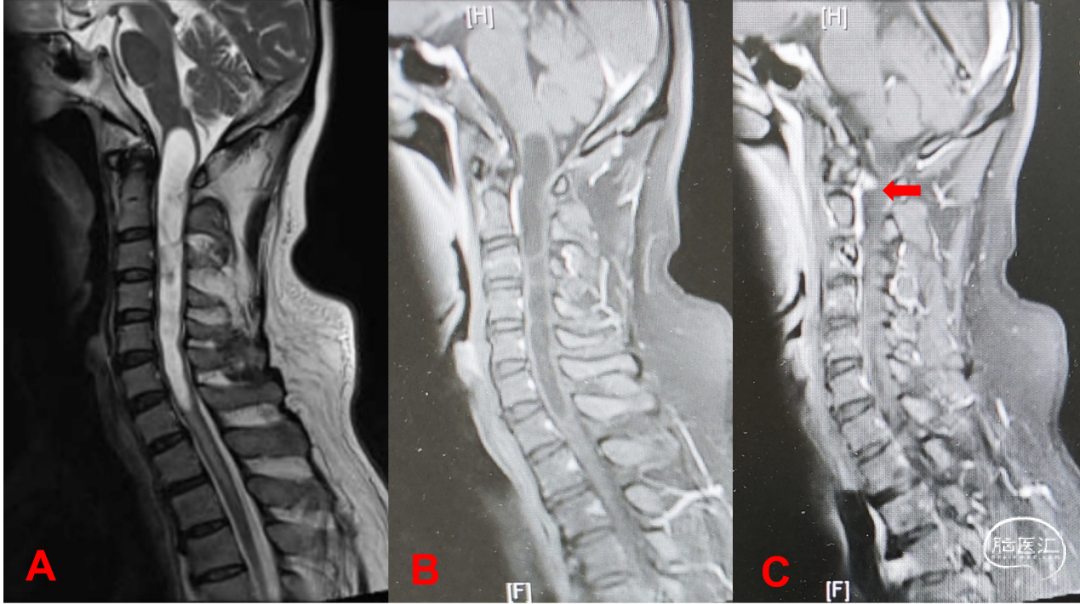

患者半年前因颈椎椎管内囊性占位,诊为“脊髓空洞症”,在外院行手术治疗(2021-08-05),术后病理:(颈髓)不除外脊髓空洞症。半年后至当地医院复查影像检查提示:颈1-7颈髓囊实性占位,囊腔较前片2021-06-12稍缩小。两月后因左侧肢体麻木,四肢末端较严重,右侧脚掌麻木,长时间行走后加重,伴左下肢乏力,至我院进一步诊治,磁共振复查提示颈髓囊肿伴实质性强化结节,偏于左侧,血管母细胞瘤考虑。门诊拟“颈髓血管母细胞瘤”收治入院。

术前检查:我院颈椎增强MRI提示:延髓至颈6水平髓内囊实性病变,增强后提示约颈1水平脊髓腹侧偏左可见明显强化小结节影,首先考虑血管母细胞瘤(图2)。颈椎CT-VRT重建提示:颈髓术后,相应颈椎附件呈术后复位重建改变(图2E)。